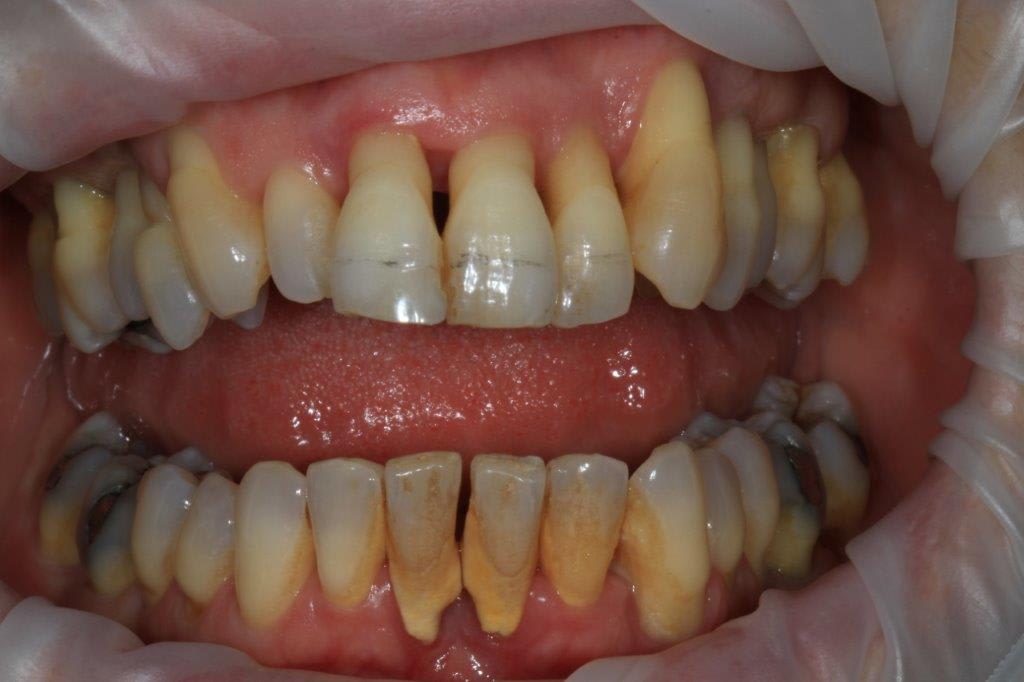

un peu de grain à moudre, toutes les critiques sont les bienvenues...

1ere séance,"nettoyage...", et après réflexion, plutôt que le nettoyage par le vide, attelle de contention pour le bloc antérieur mandibulaire, suppression de quelques contact très parasite sur les pm et canines, et réduction des incisives mandibulaire puis maxillaire... consignes de brossages / bain de bouche avec .... l'érythritol afin de ne pas mourir idiot... on verra ce que ça donne dans un cas relativement perdu d'avance.... merci Algi... enfin peut être : -))

C est dommage que l'on ne voit pas les dents en occlusion .

La 12 est en occlusion inverse et le secteur postérieur 20/30 aussi ?

Une fois de plus ce n est pas un pb Paro mais bien occlusal .

effectivement, je vois la conséquence paro d'un problème avec départ occlusal, mais peut être pas que.